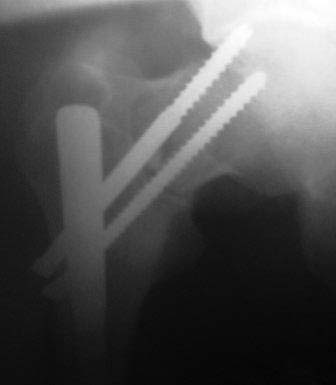

У Синтеза специально для таких двойных переломов есть латеральный бедренный гвоздь, позволяющий увеличить расстояние между гвоздем и линией перелома шейки за счет смещения кнаружи точки введения гвоздя. Во вложении - трехлетней давности пример: остеосинтез выполнен через полтора месяца после травмы, вполне удалась закрытая репозиция проксимального перелома. Единственный непонятный для меня момент такой операции - невозможность динамизации диафизарного перелома без удаления фиксаторов из головки. В представленном случае шейка срослась быстро, а вот диафиз - только после удаления верхних винтов и установки винта в динамическое отверстие в подвертельной области.

У Синтеза специально для таких двойных переломов есть латеральный бедренный гвоздь, позволяющий увеличить

Вряд ли дизайн реконструкционного стержня тут играл бы ключевую роль.

Действительно, риск неудачи меньше, если делать раздельно (шейку - винтами или DHS, диафиз ретроградно). Одной жеезкой делать труднее, а еще и без ЭОП. Но можно.

Здесь судя по снимку с дистрактором (действительно, знакомый ;-) начало было хорошее, а вот дальше... Мы бы не накладывали дистрактор таз бедро. А ввели бы спицу в области малого вертела. закрепели в дуге, сделали репозиию шейки, и сначала ее фиксировали спицами, оставив место для гвоздя. Дистрактор наложили бы за эту же спицу и в в дистальном бедре. Точку входа для этого гвоздя надо было сделать медиальнее. Чтобы знать плоскость антеверсии шейки (особенно без ЭОП это нужно, понятное дело) нужно было ввести спицу, скользя по передней поверхности шейки.

Гвоздь ввести поглубже немного, тогда и винты бы прошли в головку. А тут, похоже, варус появился еще на этапе остеосинтеза.

Тут надо переделать, конечно. Можно даже перештифтовать, но без ЭОП это очень медленно и печально, постоянно надо ждать снимки. Главное снова добиться репозиции, не торопиться, и может быть сделать раздельно.